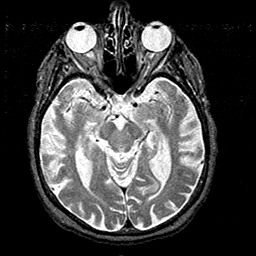

Alzheimer's disease MR T2-weighted -- Slice #19

Tour 1: Next/Previous/Start: On this slice, the atrophic hippocampus and amygdala can be seen. These structures subserve memory function, and are the sites of major damage in Alzheimer's disease.

[Home][Help][Clinical][Tour 1][Tour 2] Slice 19